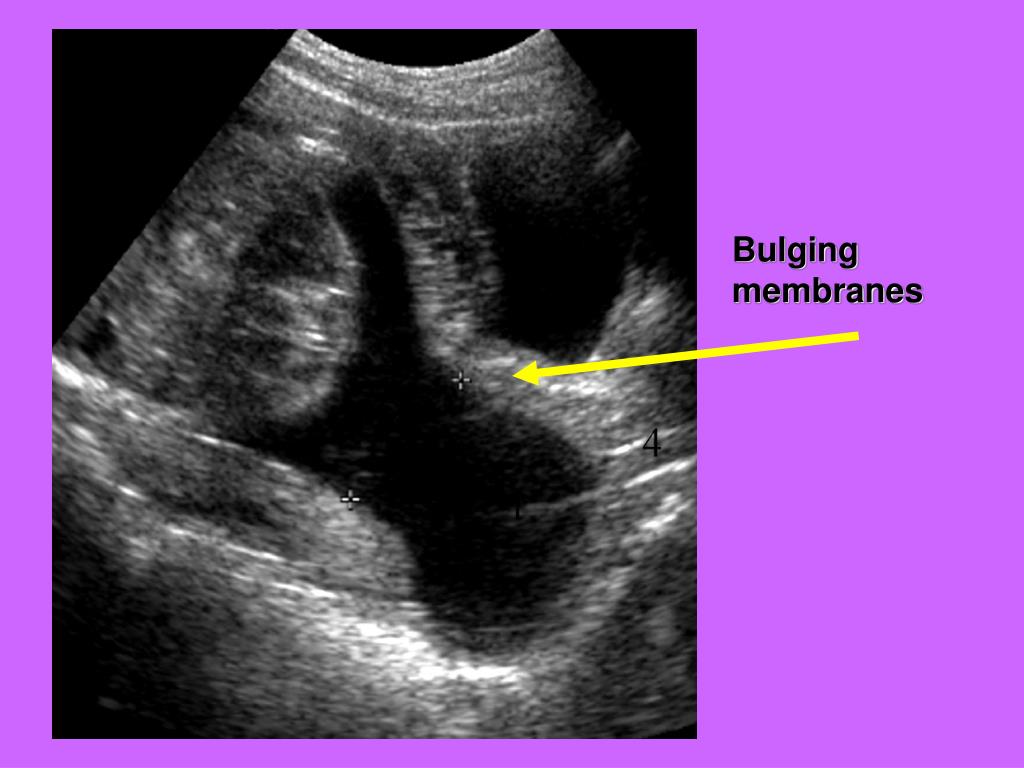

PPT Fetal Biometry PowerPoint Presentation, free download ID1266626 What Are Membranes In Pregnancy Fetal membranes or amniochorionic membranes are one of the most intriguing tissues in the intrauterine cavity that are essential for. The amniotic sac, also known as the “bag of water” or the membranes, surrounds a fetus. It’s also known as a membrane sweep. During pregnancy, the fetal membranes (i.e., amniochorionic membranes) surround the intrauterine cavity and provide. Premature rupture of. What Are Membranes In Pregnancy.